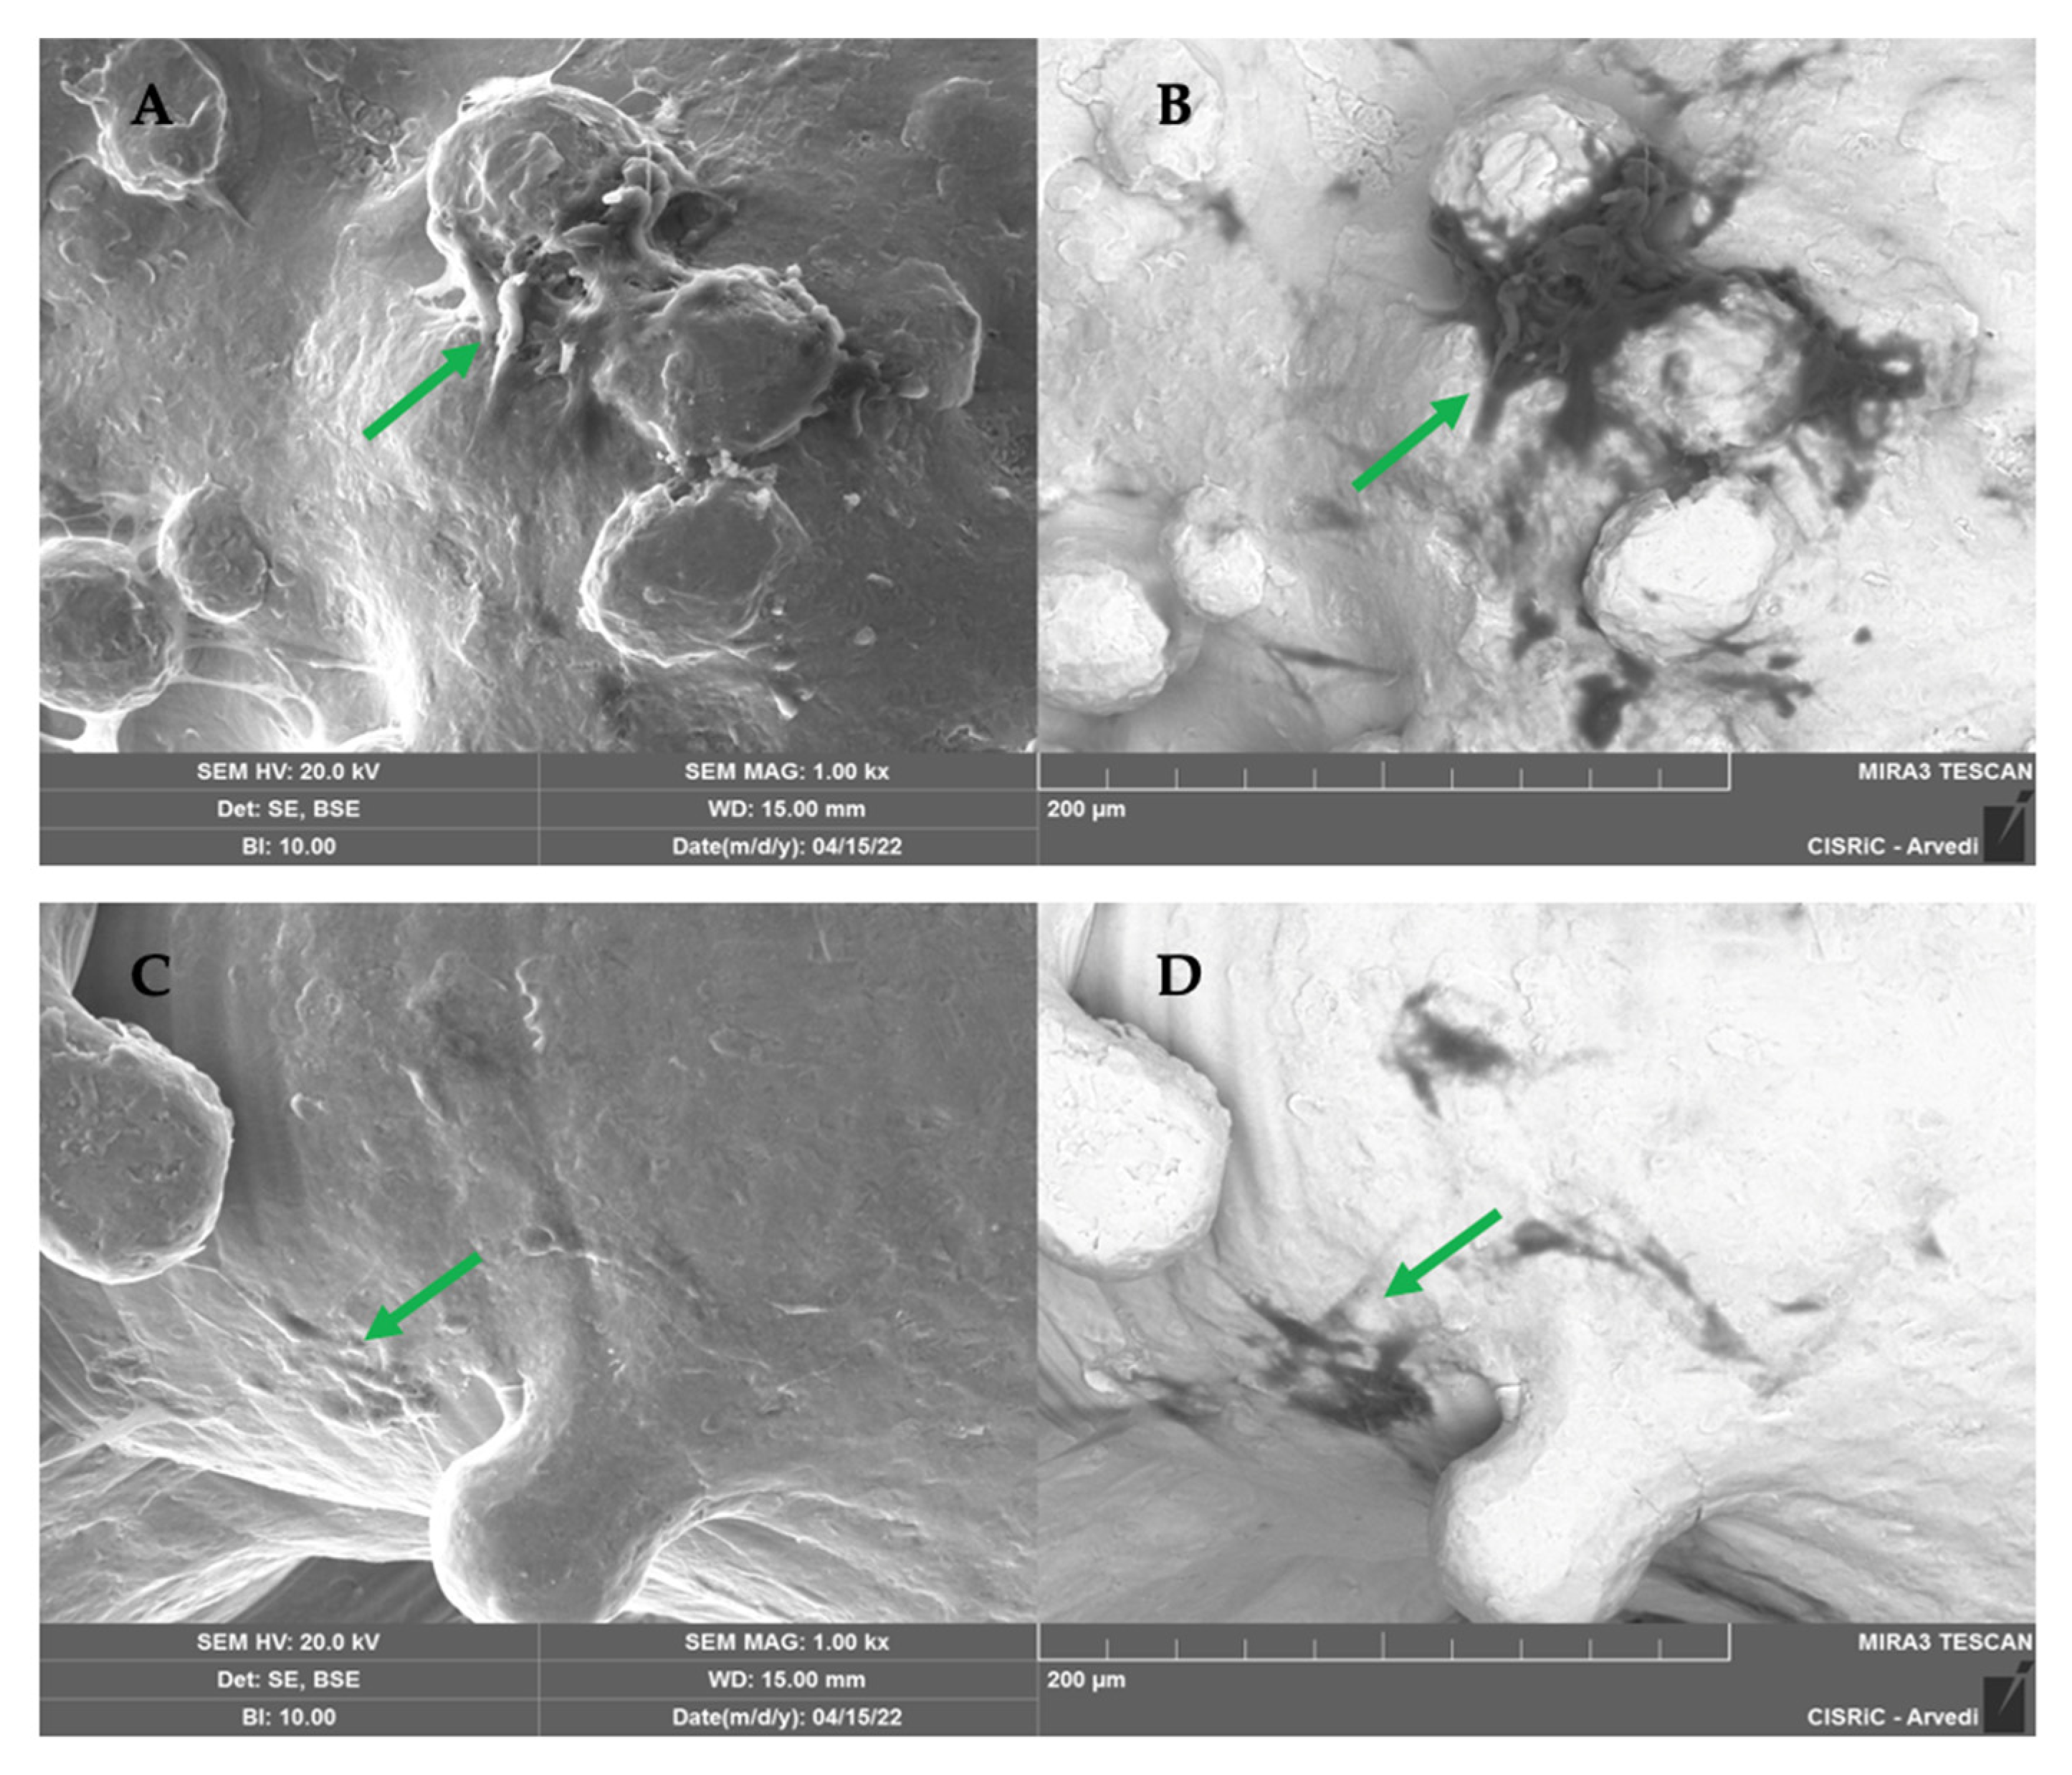

2.1.5. SEM Analysis

3. Discussion

4.10. Scanning Electron Microscope (SEM) Analysis